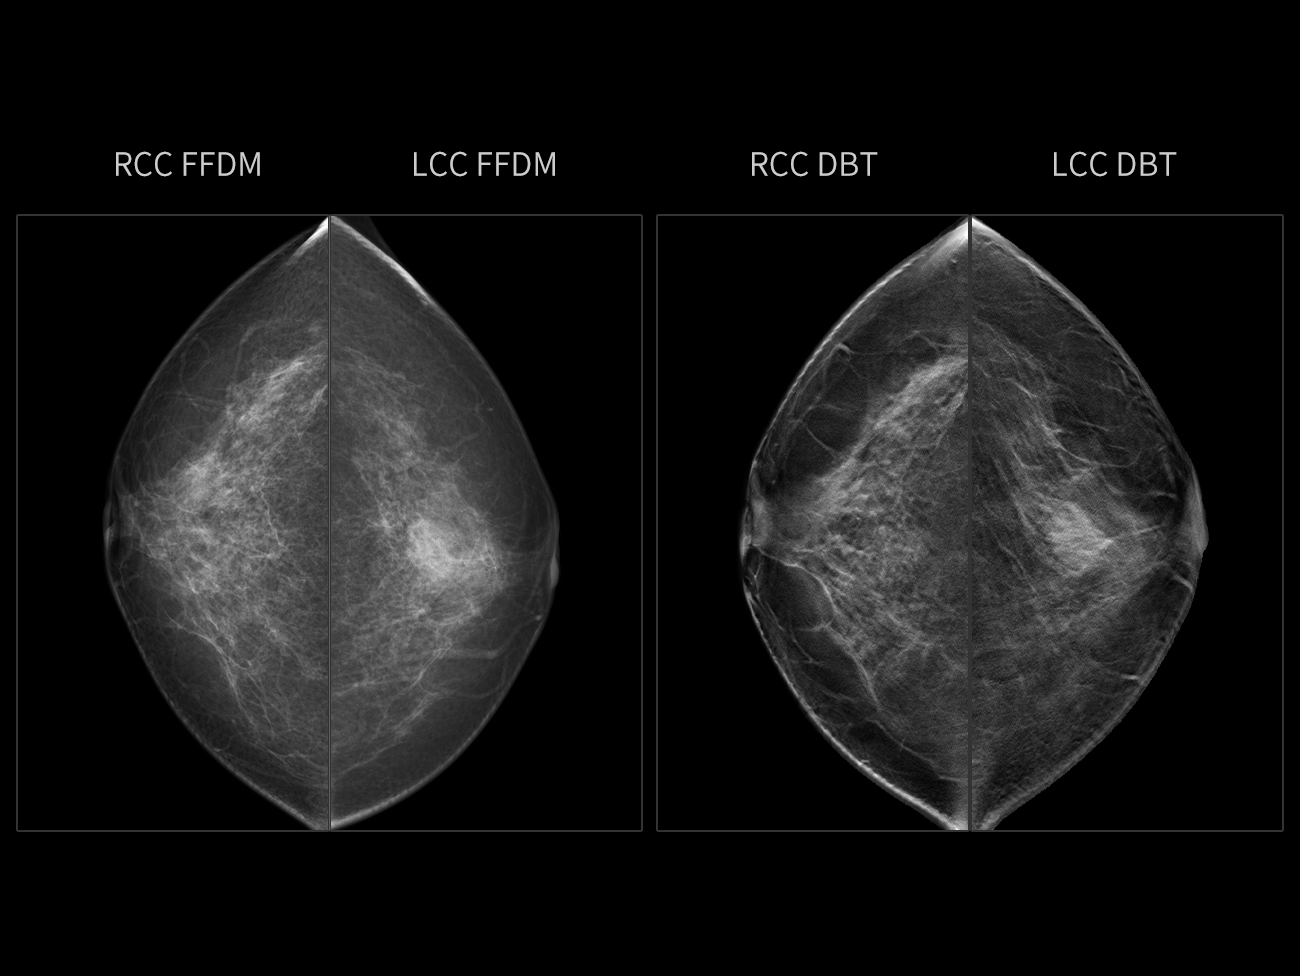

Sân fibroglandular dens, cu o grosime de 61 mm.

FFDM evidențiază clar o masă palpabilă densă, neregulată, în zona mijlocie a sânului stâng postero-inferior, cu margini neclare și lobuli vizibili. DBT arată mai clar hiperplazia glandulară, cu multiple noduli mici și câteva calcificări punctiforme.